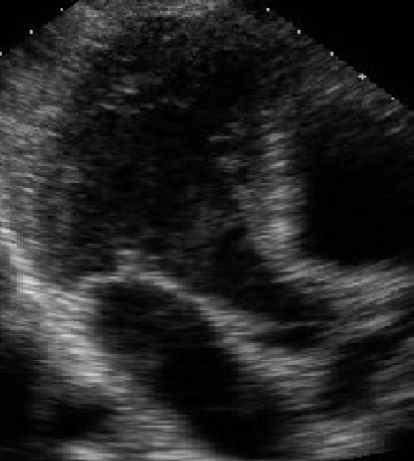

<p>What view is this?</p>

Apical 4 Chamber